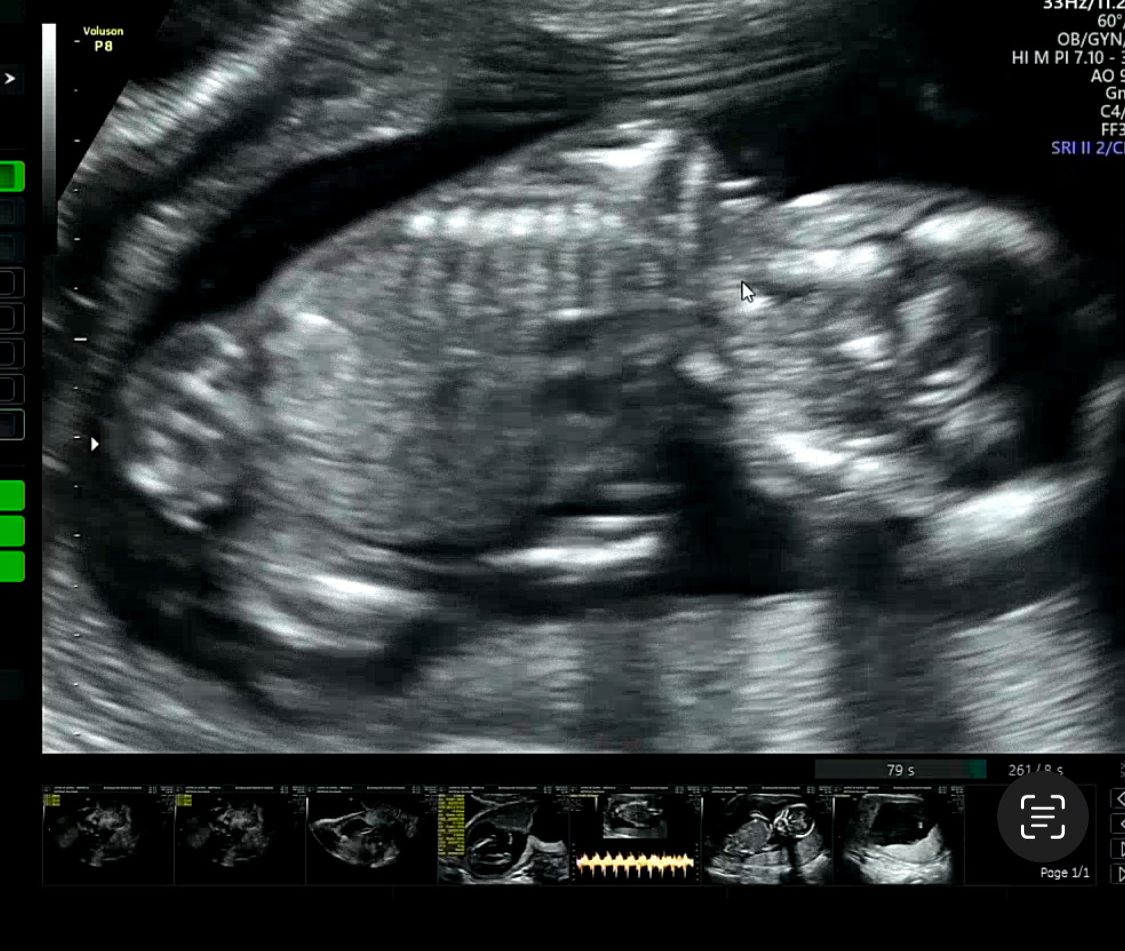

온김에 초음파 봐주신대서 봤는데

애기가 너무 안 움직여서 속상했다

울 복덩이도 덥나ㅠㅠ 아픈가.. 힘든가부다하고 걱정이 이만저만..

다복이도 원래 엄청 꼼지락대는데

아프니까 잘 움직이지도 않고..

엄마가 미안........... 가여워라..